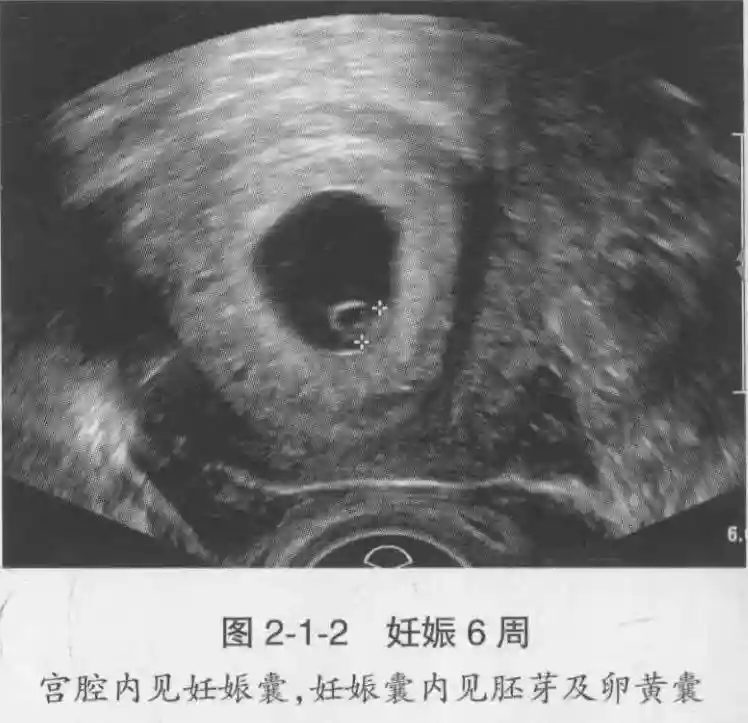

1??妊娠囊:早期妊娠囊:正常妊娠囊位于宮腔上段,表現(xiàn)為宮腔內(nèi)圓形或橢圓形的無(wú)回聲區(qū),周邊為完整的、厚度均勻的強(qiáng)回聲環(huán),強(qiáng)回聲環(huán)厚度≥2mm,強(qiáng)回聲是妊娠絨毛的回聲,隨著妊娠囊的增大,形成特征性的“雙環(huán)征” ,10周以后消失。正常的妊娠囊增長(zhǎng)速度是平均 1 mm /d。

2??卵黃囊:是妊娠囊內(nèi)第一個(gè)解剖結(jié)構(gòu),直徑<7mm。表現(xiàn)為小環(huán)狀,中央為無(wú)回聲,囊壁薄,內(nèi)透聲好。卵黃囊位于胚胎旁胚外體腔內(nèi)。卵黃囊通常在孕5-6周時(shí)出現(xiàn),5-10周穩(wěn)步增長(zhǎng),一般不超過(guò)7mm,至12周消失。妊娠囊的大小與卵黃囊之間有一定關(guān)系,妊娠囊平均直徑> 8 mm 時(shí),經(jīng)陰道超聲均應(yīng)顯示卵黃囊,妊娠囊平均直徑> 18 mm 時(shí),經(jīng)腹超聲均應(yīng)顯示卵黃囊。